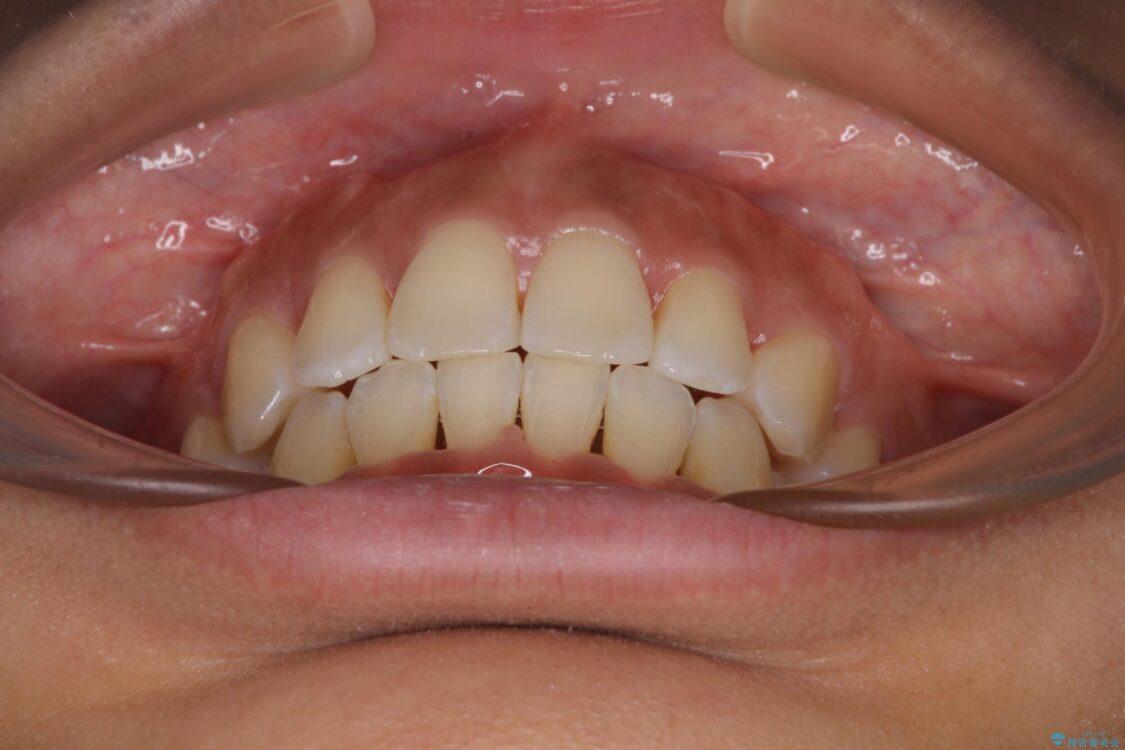

下唇が突き出るような口元の突出感が気になるとのことで来院された患者様です。

上下顎ともに前突した歯列であったので、上下ともに左右の第1小臼歯4本を抜歯し、ワイヤー装置にて矯正治療を行うこととしました。

治療前

• 抜歯矯正で唇を閉じやすく 目立たないワイヤー装置 治療前画像